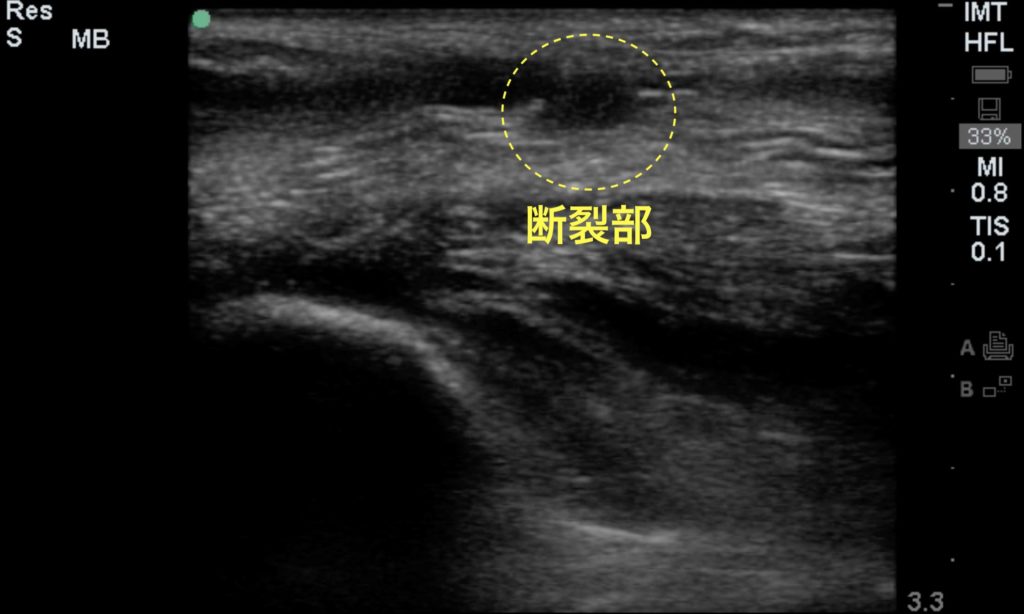

【#30】救急外来。右足痛。考えられる疾患は何か?

アキレス腱断裂

アキレス腱断裂の身体所見としてはトンプソン徴候や陥凹の触知などが知られているが、いずれも感度は十分ではない。超音波では、アキレス腱断裂を視覚的に捉えることができる。断裂部では下の画像のように繊維の不連続な部分が容易に見て取れる。身体所見で分かりにくい不全断裂の場合でも異常として覚知することができる。